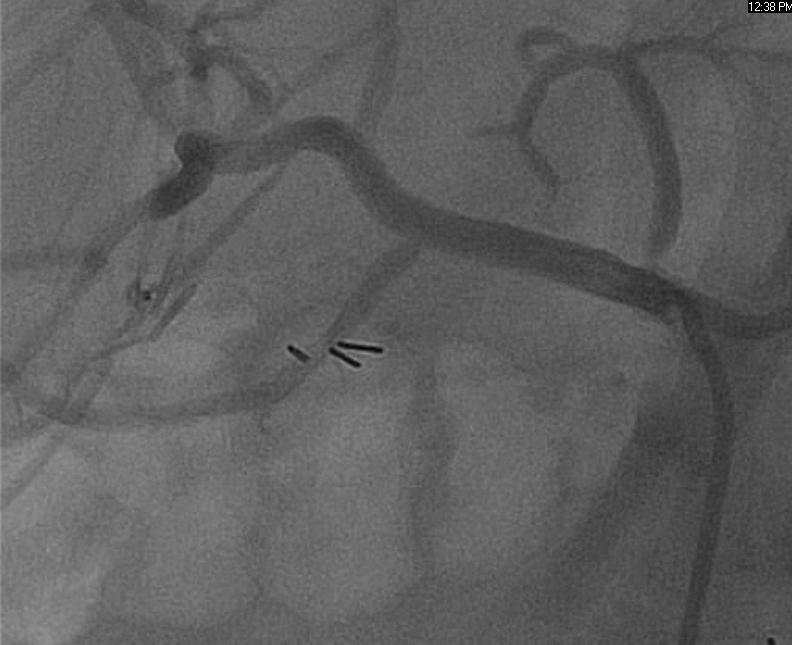

Sequential drug-eluting stents were placed and post-dilated with a good result (Fig 2, 3).